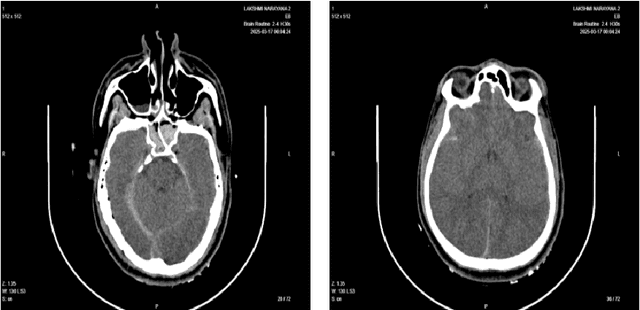

Abstract:Background: Intracranial bleeding (IB) is a life-threatening condition caused by traumatic brain injuries, including epidural, subdural, subarachnoid, and intraparenchymal hemorrhages. Rapid and accurate detection is crucial to prevent severe complications. Traditional imaging can be slow and prone to variability, especially in high-pressure scenarios. Artificial Intelligence (AI) provides a solution by quickly analyzing medical images, identifying subtle hemorrhages, and flagging urgent cases. By enhancing diagnostic speed and accuracy, AI improves workflows and patient care. This article explores AI's role in transforming IB detection in emergency settings. Methods: A U-shaped 3D Convolutional Neural Network (CNN) automates IB detection and classification in volumetric CT scans. Advanced preprocessing, including CLAHE and intensity normalization, enhances image quality. The architecture preserves spatial and contextual details for precise segmentation. A dataset of 2,912 annotated CT scans was used for training and evaluation. Results: The model achieved high performance across major bleed types, with precision, recall, and accuracy exceeding 90 percent in most cases 96 percent precision for epidural hemorrhages and 94 percent accuracy for subarachnoid hemorrhages. Its ability to classify and localize hemorrhages highlights its clinical reliability. Conclusion: This U-shaped 3D CNN offers a scalable solution for automating IB detection, reducing diagnostic delays, and improving emergency care outcomes. Future work will expand dataset diversity, optimize real-time processing, and integrate multimodal data for enhanced clinical applicability.